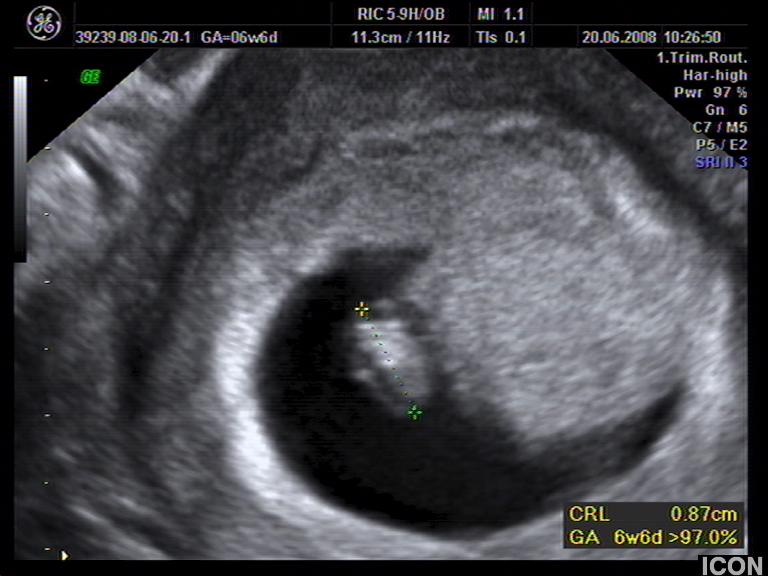

Ενδοκολπικός U/S έσω Γεννητικών Οργάνων

Αυχενική διαφάνεια

Η αυχενική διαφάνεια (ΑΔ) είναι η συλλογή υγρού στον τράχηλο του εμβρύου και συγκεκριμένα ανάμεσα στο δέρμα και στους ιστούς που καλύπτουν τη σπονδυλική στήλη.